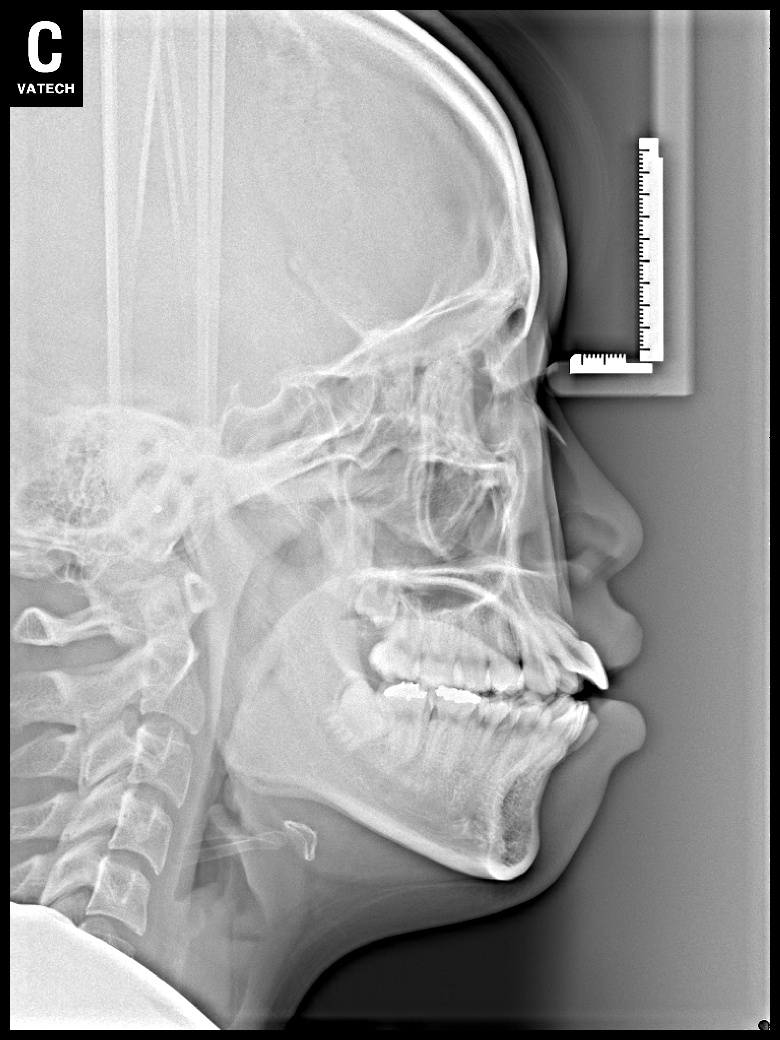

치료 후 사진입니다.